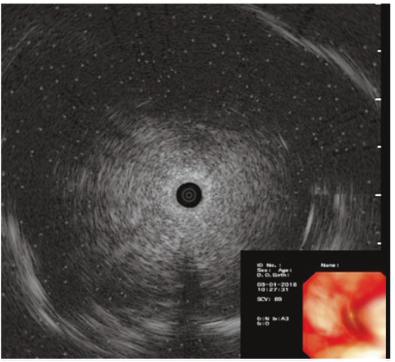

EBUS-GS检查(2018-01-09):见右下叶前基底段不规则回声区,密度欠均匀,行刷检及活检(图2)。

图2支气管镜EBUS-GS检查见右下叶前基底段不规则回声区,密度欠均匀